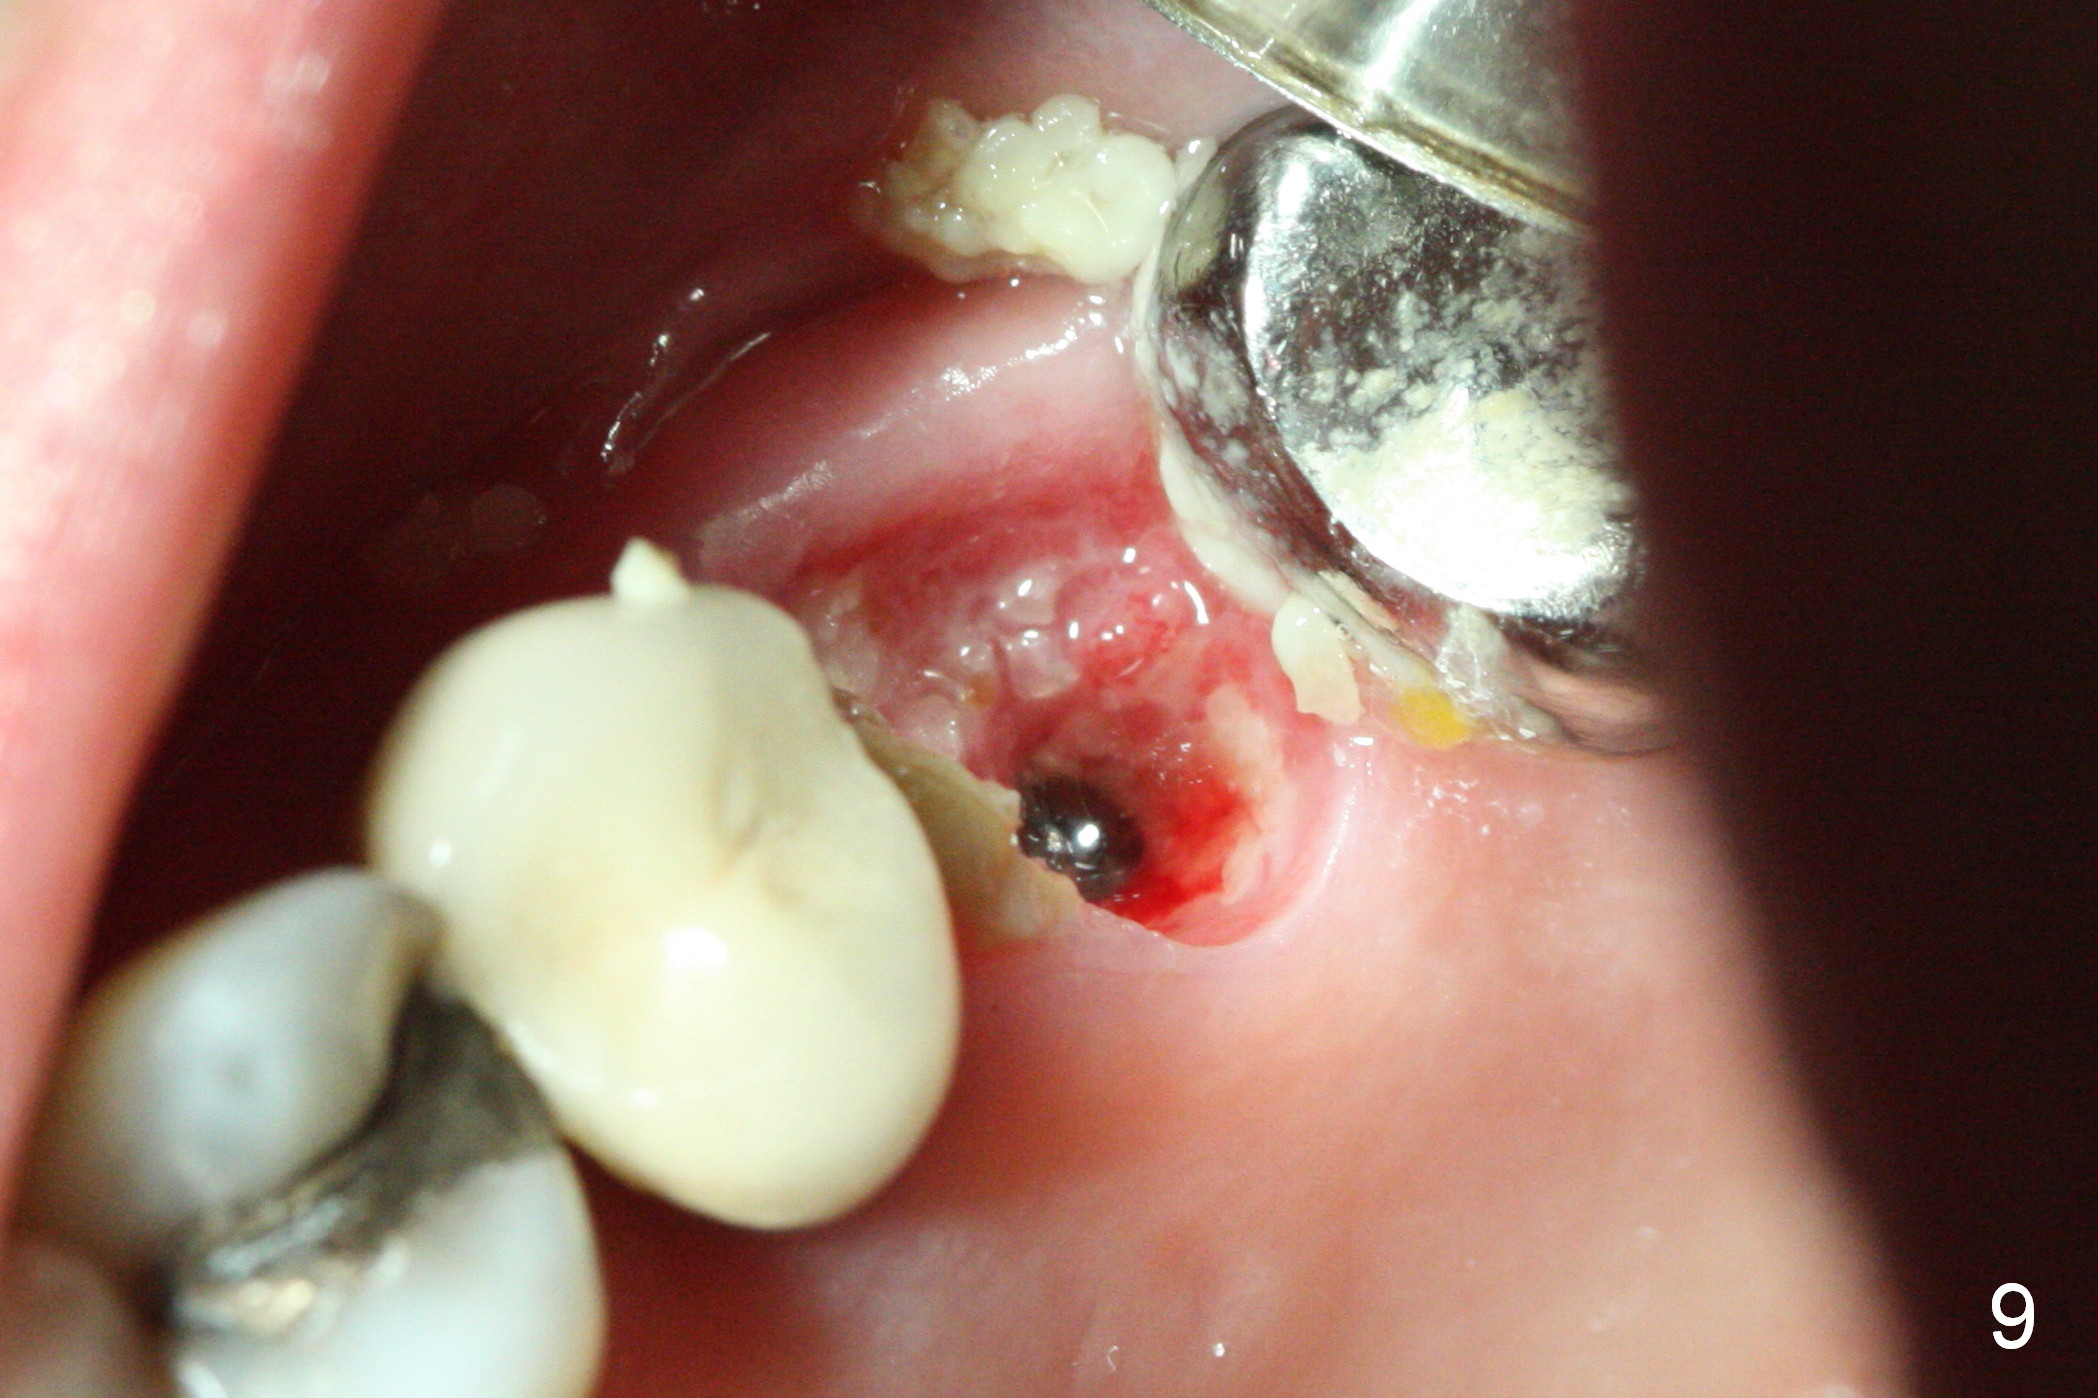

The patient is doing well 9 days postop. The immediate provisional is loose and over-sized. It is removed for trimming and reline; the socket and bone graft (Fig.8 *) are healing. It appears that an angled abutment is required next time of provisional revision. When an angled abutment is being placed 23 days postop (Fig.9), it appears to wiggle the implant due to its long leverage. Instead a healing abutment is placed. The implant is unstable 4.5 months postop with seemingly excessive bone-implant gap (Fig.10 <). The 5.5x9 mm implant is removed. A 5x17 mm tap is used to change the trajectory and sinus lift, followed by 6x17 one (Fig.11). Finally a 6x14 mm tissue-level implant is placed with insertion torque > 50 Ncm (Fig.12; vs. <20 Ncm (Fig.7,10)) and improved trajectory. An immediate provisional is fabricated to prevent the mesial drifting of the tooth #15 (Fig.13 P (*: occlusal clearance)). By using the taps and placing the longer implant, the sinus lift is more obvious (compare Fig.10 and 12 (*)). Sinus lift remains evident 3.5 months postop (Fig.14) with apparently osteointegration (Fig.15).